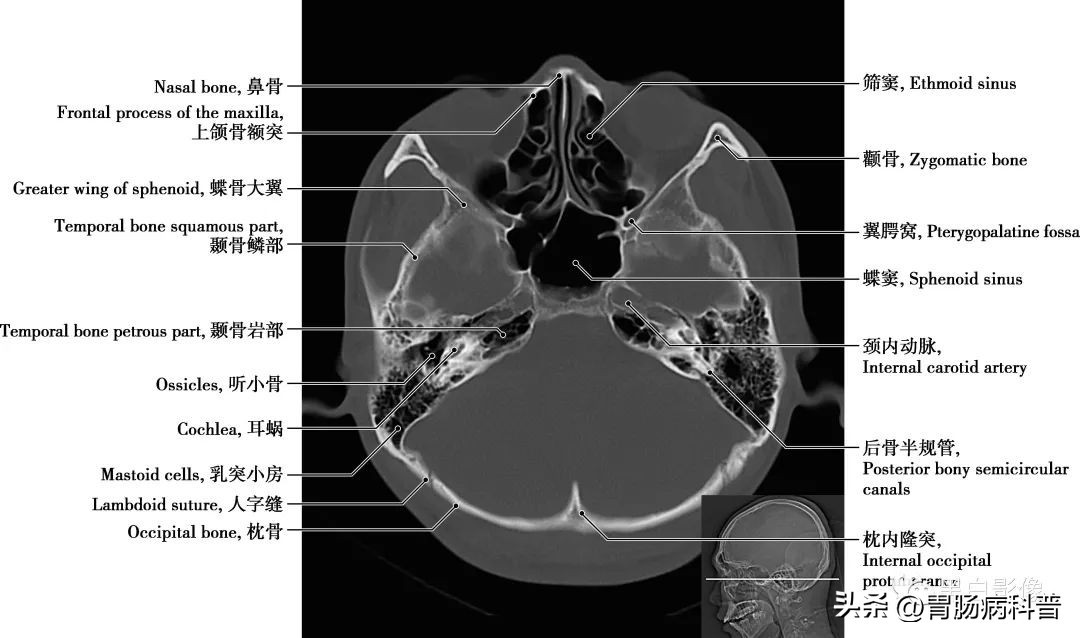

图1-2-16 经第四脑室侧孔轴位切面

颈内动脉 分为颅外段又称颈段,自颈总动脉分叉处至颅底。颅内段分为七段:C 1 颈段、C 2 岩段、C 3 破裂(孔)段、C 4 海绵窦段、C 5 床段、C 6 眼段和C 7 交通段。分支分布于视器和脑

图1-2-17 经第四脑室正中孔轴位切面

翼腭窝 位于颞下窝前内侧,上颌骨(或上颌窦后壁)与翼突之间,前界为上颌骨,后界为翼突及蝶骨大翼前界,顶为蝶骨体下面,内侧壁为腭骨的垂直部。窝内有颌内动脉、上颌神经及蝶腭神经节。翼腭窝向外经翼上颌裂通颞下窝,向内上经蝶腭孔通鼻腔,向前经眶下裂通眼眶,向后上经圆孔通颅中窝,借翼管通颅底外面,向下移行于腭大管、腭大孔通口腔